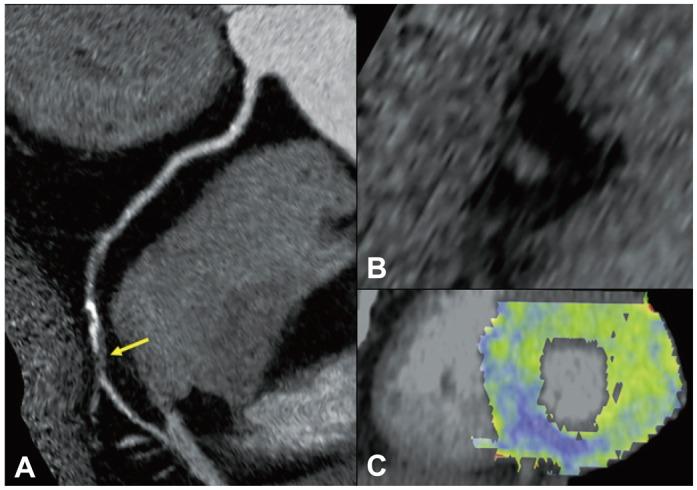

Vascular surgery carries high operative risk. Recently developed cardiac computed tomography (CT) provides excellent imaging of coronary artery disease (CAD), as well as myocardial perfusions. We investigated the role of stress perfusion CT with coronary computed tomography angiography (CCTA) using 128-slice dual source CT (DSCT) in preoperative cardiac risk evaluation.

Patients scheduled for vascular surgery were admitted and underwent the adenosine stress perfusion CT with CCTA using DSCT. Patients who presented with unstable angina, recent myocardial infarction, decompensated heart failure, or renal failure were excluded. Stress perfusion CT was first acquired using sequential mode during adenosine infusion, after which, scanning for CT angiography was followed by helical mode. Perioperative events were followed up for 1 month.

Ninety-one patients completed the study. Most patients (94.5%) had coronary atherosclerosis, with 36 (39.6%) patients had more than 50% coronary artery stenosis. Perfusion defects with significant stenosis were found in 12 cases (13.2%). Revascularization after DSCT was rarely performed. Four patients (4.4%) experienced cardiac events in the perioperative period: two experienced heart failure and two had non-fatal myocardial infarction.